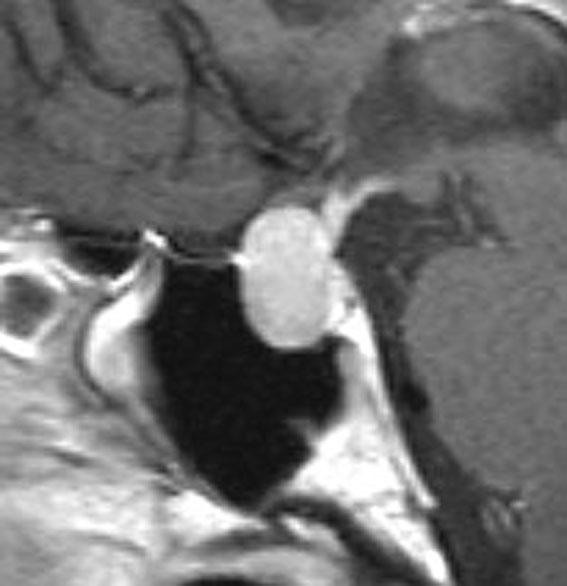

とても小さな腫瘍(微小腺腫) microadenoma

1cm以下の小さなものを微小腺腫といいます。ホルモンを異常に分泌する腫瘍は摘出する必要がありますが,そうでないものは治療の必要がありません。微小腺腫を数年観察しても増大する確率は10%くらいです。逆に,それ以上に大きなものだと,50%くらいの確率で増大します。

日本で汎用されているものでは最も解像力が高い3テスラMRIで撮影された,ガドリニウム増強像です。左側の画像では下垂体の大きさと形は正常に見えます。画像を調整すると,下垂体の内部,右端(黄色の矢印の先)に6mmくらいの小さな腺腫がみつかりました。MRIの性能がよくなったことによって数mmの小さなものも診断できるようになりました。